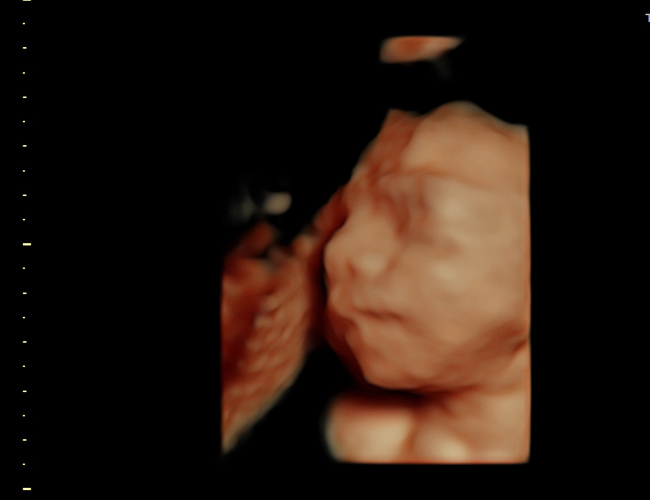

4D Fetal Imaging

HD, 4D and 3D ultrasound in Loving Arms Birth and Wellness Center in Ocala Florida.